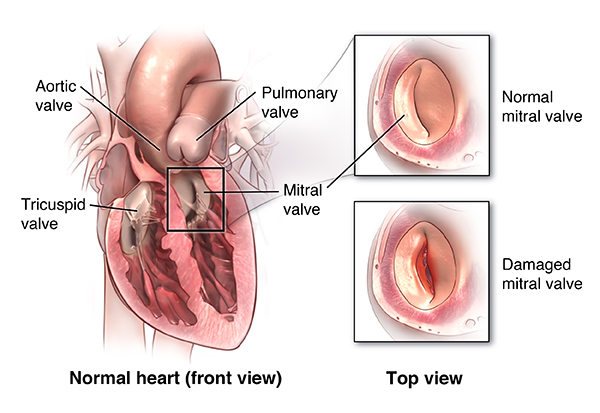

Overview

Package includes:

Days in hospital : 7 to 8 Days (For patient and one attendant)

Days in hotel : 12 Days (For patient and one attendant)

Room type in hospital : Shared

Room type in hotel : Private

Hotel category: General

Value added benefits of the Mitral Valve Replacement:

Ø Doctor consultation charges

Ø Lab tests and diagnostic charges

Ø Room charges inside hospital during the procedure

Ø Surgeon Fee

Ø Cost of implant

Ø Nursing charges

Ø Hospital surgery suite charges

Ø Anesthesia charges

Ø Routine medicines and routine consumables (bandages, dressings etc.)

Ø Food and Beverages inside hospital stay for patient and one attendant.

Extra benefits:

ü Interpreter

ü Visa assistance

Ø Site tourism of the city

Ø Follow up with the doctor

Ø Airport pick up and drop

Ø Free online consultation with the doctor

Ø Priority appointments with the doctor

Ø Room upgrade from sharing to private

Overview

Package includes:

Days in hospital : 7 to 8 Days (For patient and one attendant)

Days in hotel : 12 Days (For patient and one attendant)

Room type in hospital : Shared

Room type in hotel : Private

Hotel category: Standard

Value added benefits of the Aortic Valve Replacement:

Overview

Package includes:

Days in hospital : 7 to 8 Days (For patient and one attendant)

Days in hotel : 12 Days (For patient and one attendant)

Room type in hospital : Shared

Room type in hotel : Private

Hotel category: Standard

Value added benefits of the Tricuspid Valve Replacement:

Overview

Package includes:

Days in hospital : 7 to 8 Days (For patient and one attendant)

Days in hotel : 14 Days (For patient and one attendant)

Room type in hospital : Shared

Room type in hotel : Private

Hotel category: Standard

Value added benefits of the Double Valve Replacement:

Overview

Package includes:

Days in hospital : 7 to 8 Days (For patient and one attendant)

Days in hotel : 14 Days (For patient and one attendant)

Room type in hospital : Shared

Room type in hotel : Private

Hotel category: Standard

Value added benefits of the Single Valve Replacement:

Overview

Package includes:

Days in hospital : 6 to 7 Days (For patient and one attendant)

Days in hotel : 14 Days (For patient and one attendant)

Room type in hospital : Shared

Room type in hotel : Private

Hotel category: Standard

Value added benefits of the Triple Valve Replacement or Repair: